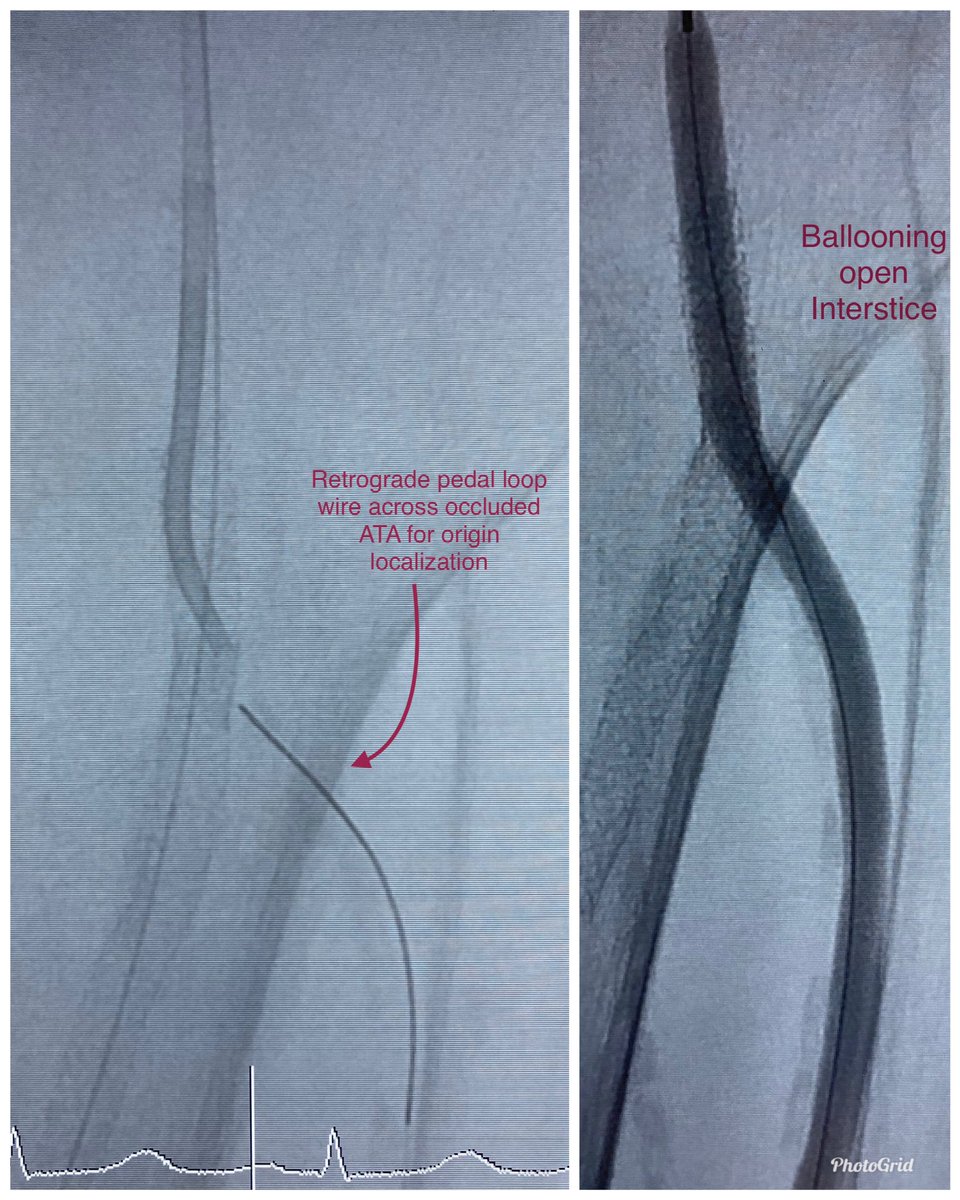

Dorsal foot wound, stent jailing origin of occluded AT, unable to retrograde puncture occluded AT. Pedal loop retrograde traversal of occluded AT to localize its origin followed by antegrade traversal of stent interstices, balloon, stent

@SoFloVIR@OmoKinju@SIRRFSpic.twitter.com/P2QFYbHgG7